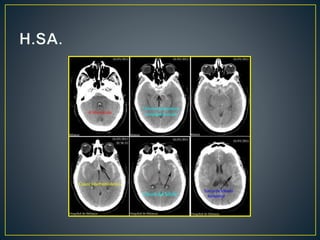

Este documento resume los pasos para evaluar un sangrado subaracnoideo. Inicialmente se realizan estudios clínicos e imagenológicos como una TC sin contraste para detectar sangre y determinar su origen. Luego, la Escala de Fisher clasifica la cantidad y ubicación de la sangre. Si la TC es normal pero los síntomas sugieren sangrado, una arteriografía cerebral puede identificar la causa. Finalmente, se enumeran las posibles complicaciones neurológicas y extra-neurológicas.